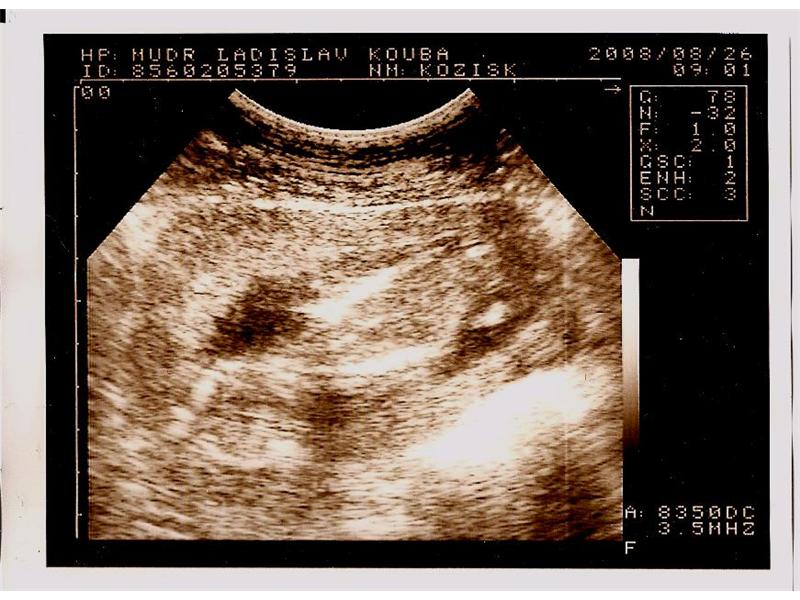

10.týden

2 fotografií